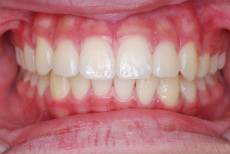

写真で確認できますように上あごの左右側12才臼歯がきちんと生えています。この噛み合わせに至るまで、本症例では固定式矯正装置での本格的矯正治療はせずにI期治療のみで終了しています。

せめてこの12才臼歯がしっかり生えてくるまでは治療の終了を急がずにじっくりと待つべし、ということです。